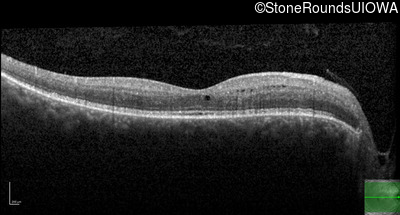

Optical Coherence Tomography - Left - 20/20 -1

Exemplar / OCT Stack